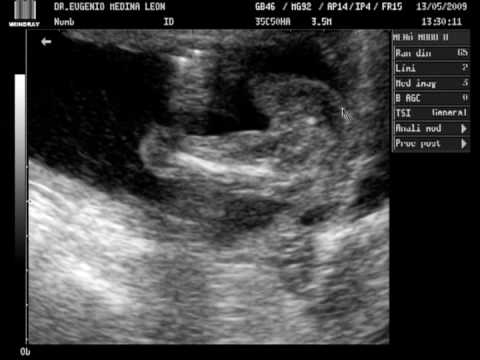

El Blog De Santiago Emiliano..: Segundo Ultrasonido